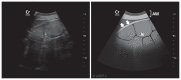

The purpose of this study was to develop a method for identification of the pylorus, in lactating Holstein cows, based on ultrasound examination and the use of external anatomical landmarks such as the mammary vein (anulus venae subcutaneae abdominis). An ultrasound method based on successive identification of 4 internal anatomical landmarks was developed. The procedure was performed 157 times, on clinically healthy lactating Holstein cows, with a portable ultrasound machine equipped with a 3.5 MHz curvilinear probe. The pylorus was identified with a success rate of 98.7% (155 times out of 157 procedures). The average position of the pylorus was noted near the entrance of the right mammary vein, with a craniocaudal and dorsoventral dispersion. This ultrasound method of identifying the pylorus is simple, effective, and rapid.